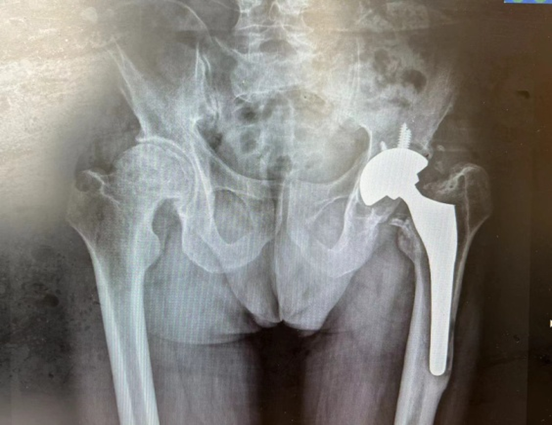

由于充分的术前设计及术中配合,手术顺利。术后,X光拍片显示假体位置满意,双下肢等长。

( 术后X光片 )